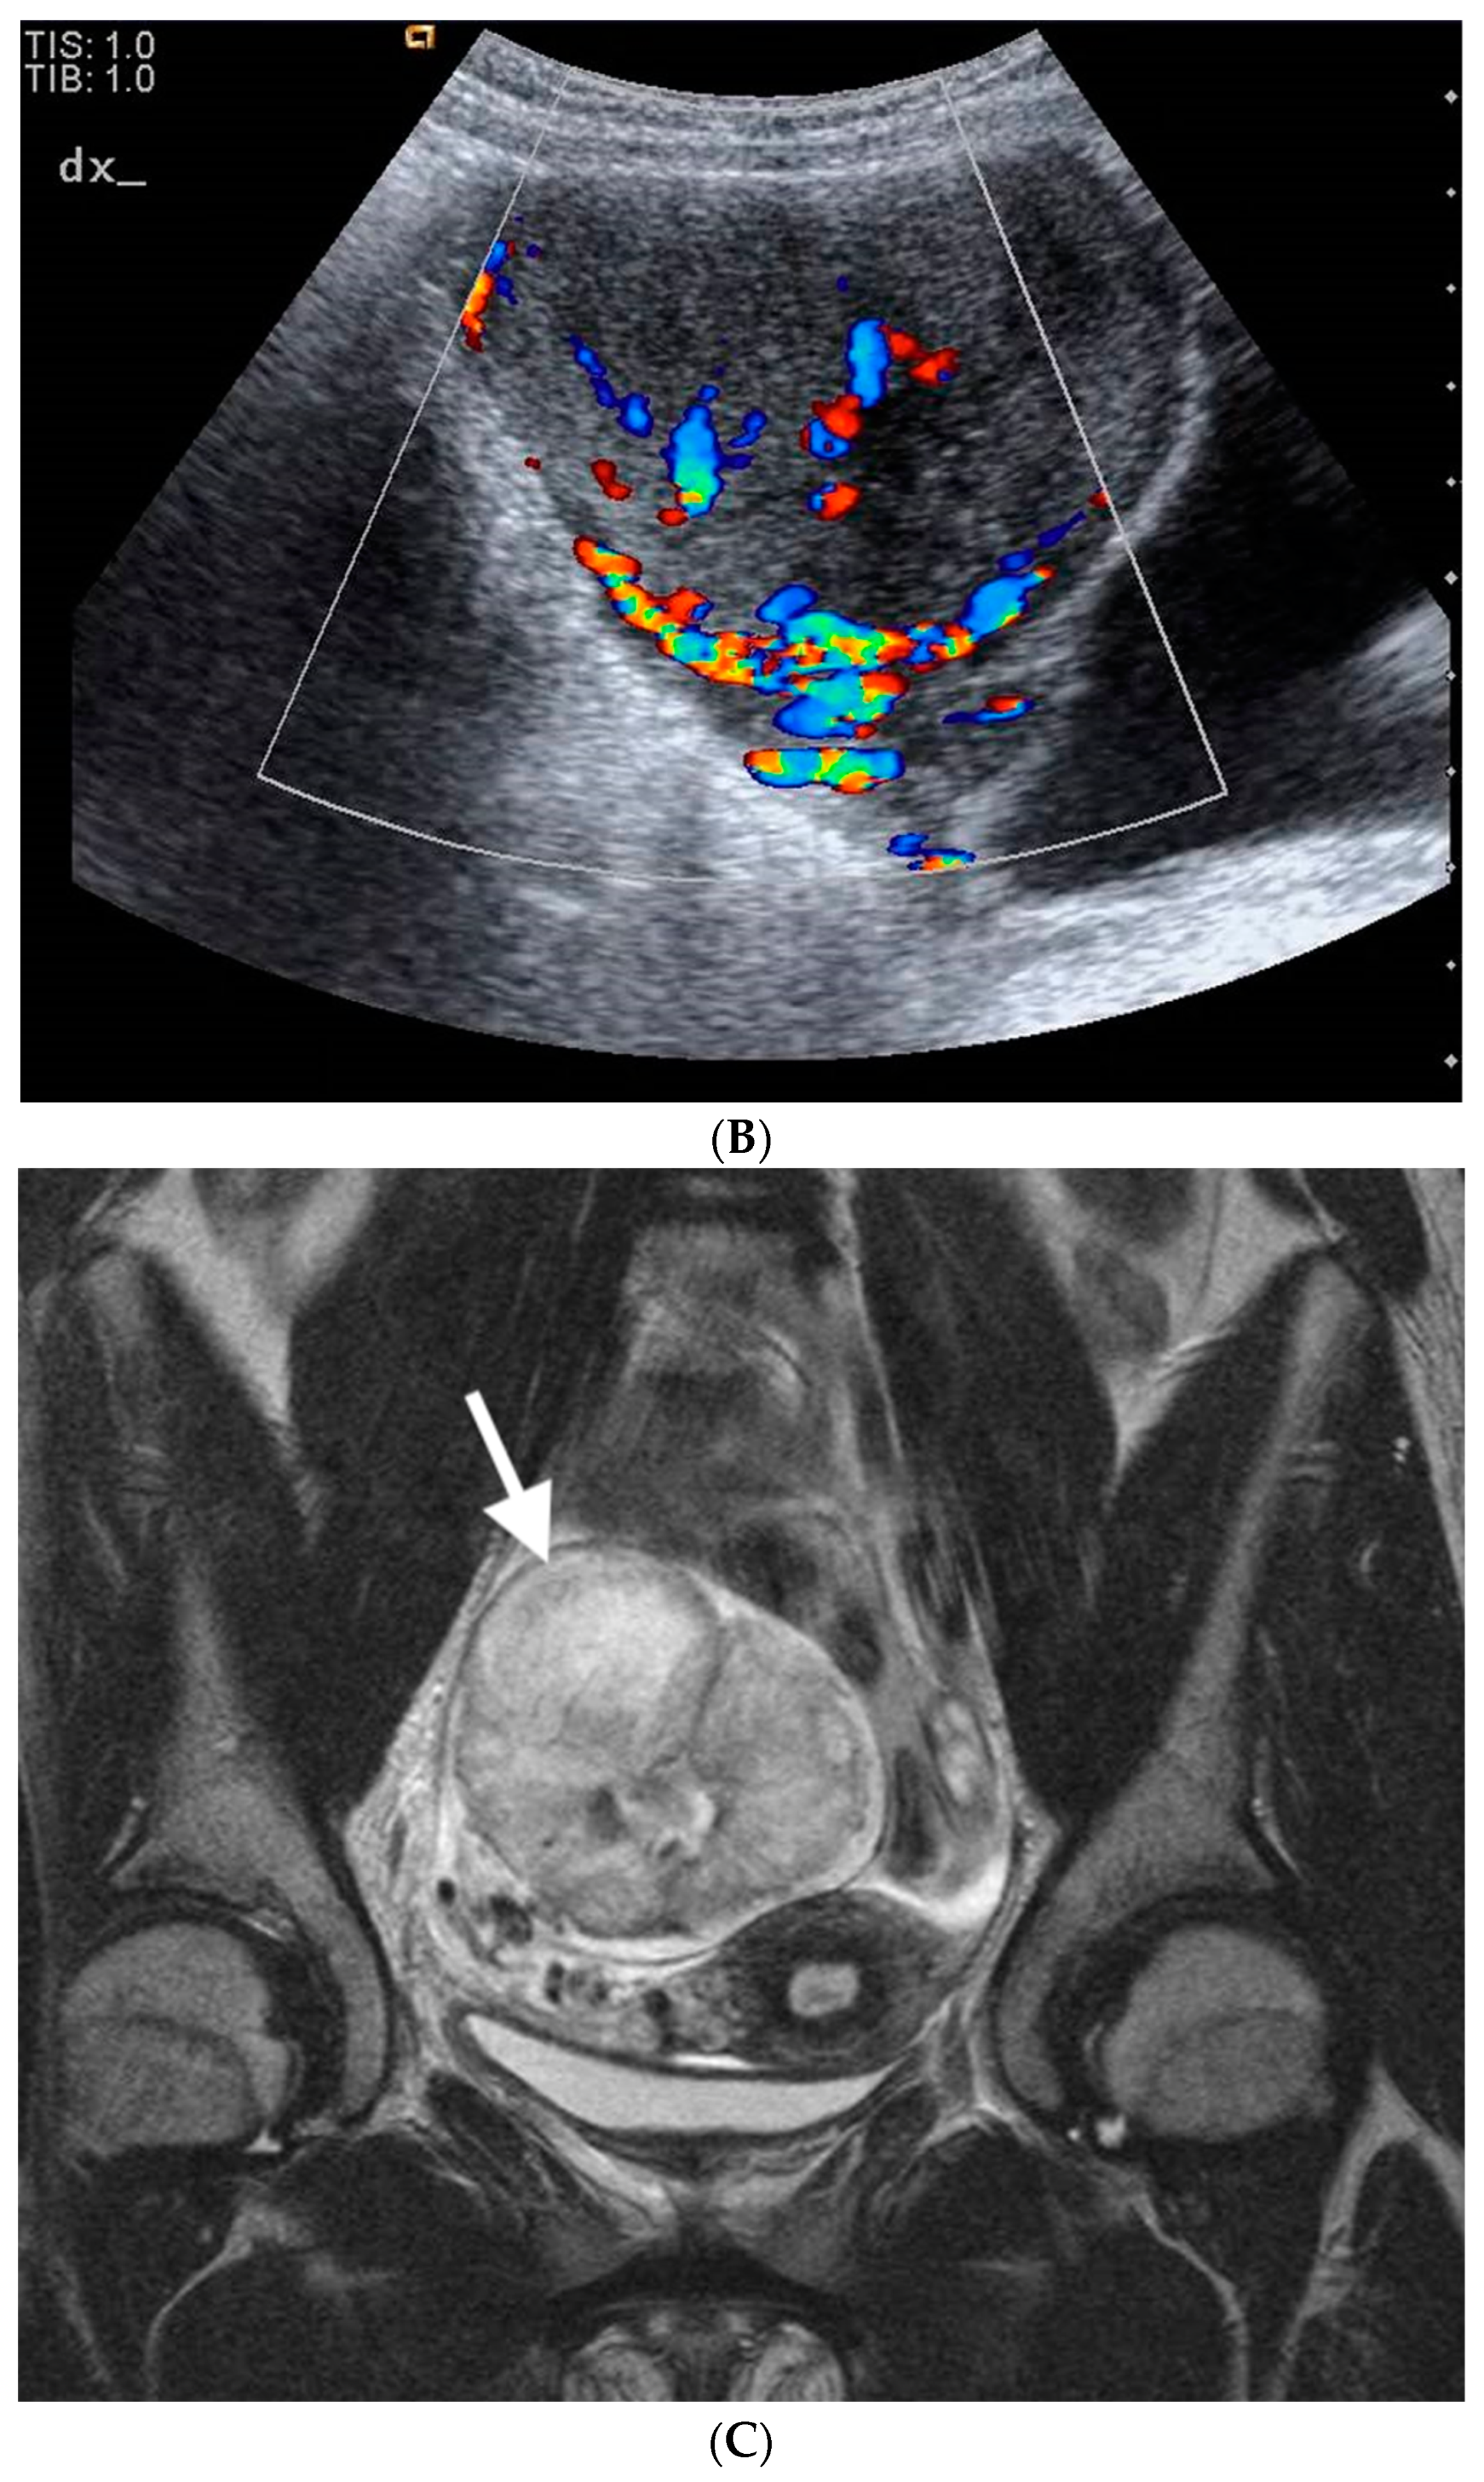

3.1. Case 1

3.2. Case 2

3.3. Case 3